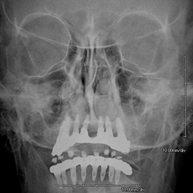

Técnica mediante la cual, utilizando rayos X, se obtienen imágenes del cráneo para su estudio. Indicaciones: traumatismo, cierre precoz de suturas craneales. - RX Senos Paranasales

Técnica mediante la cual, utilizando rayos X, se obtienen imágenes de los senos paranasales para su estudio. Indicaciones: dificultad respiratoria nasal, tos crónica, cefalea, mucosidad. - RX ATM (Articulación Temporo-Mandibular)

- Paranasal Sinuses X-ray

This technique uses X-ray rendered imaging for examining the paranasal sinuses. Indicated for: headache, chronic cough.